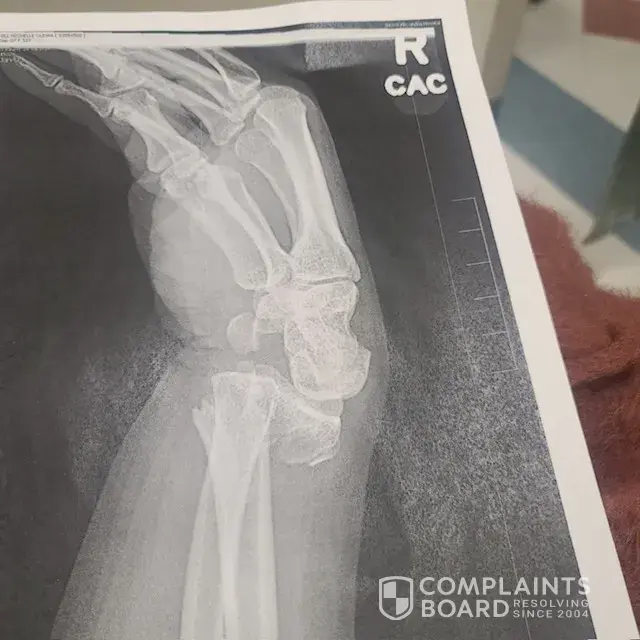

Slip and Fall - In store parking lot located at Aldi on Duke Street, Alexandria VA

On January 5, 2024, at 6:45pm upon walking out of the ALDI store I slipped and fell fracturing my right wrist severely. It is unclear of the cause of the fall, but I am reporting this incident so the cameras can be reviewed. The incident occurred at the ALDI's located at 4580 Duke Street, Alexandria VA. I did not purchase a lot of items and was not...